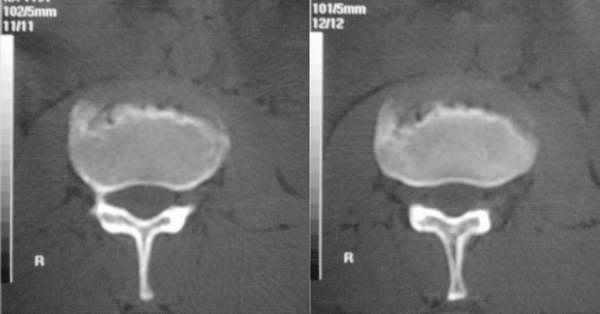

做间盘时偶而发现,请大家发表意见,平扫机器,图象不是很好请大家包涵

青年性驼背,该病主要发生于椎间软骨。好发于12-18岁,当过度负重时,在椎间盘的先天性薄弱处将发生琗裂,髓核疝入,形成许莫氏结节。本例见髓核疝入l2椎体前下缘的典型表现,且见椎间盘真空征。

定位像显示l2椎体下缘前部局限性凹陷性改变,局部骨皮质硬化,未见明显骨质破坏,各椎间隙略变窄. ct横断扫描显示椎体前缘不光整,呈退行性改变表现,未见骨质破坏,软组织肿块等异常,双侧腰大肌正常.

考虑:腰椎及椎间盘退行性改变(l2前缘系许莫氏结节+扫描层面与椎体下缘不平行所致).